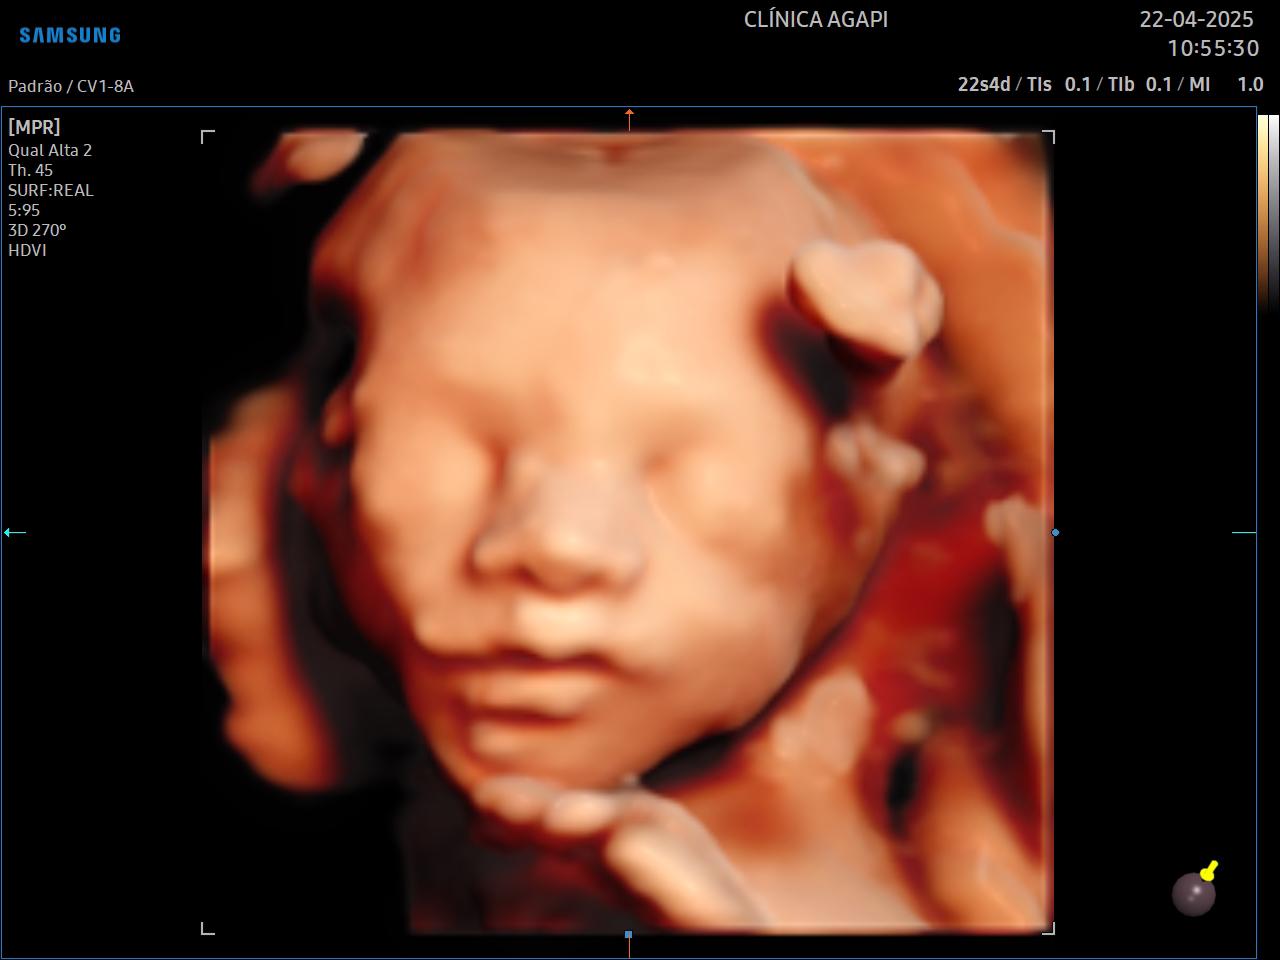

O 3D é realizado com um transdutor especial que reconstrói a superfície adquirida em uma imagem de 3 dimensões, estática. Já o 4D permite visualizar essas imagens com movimento do bebê em tempo real. Com a tecnologia HD live temos a cor do feto que dá a impressão da cor da pele.

A capacidade de aquisição de uma boa imagem tridimensional (3D/4D) depende de vários fatores, dentre eles: quantidade de líquido amniótico, posição fetal, inserção placentária, espessura do tecido celular subcutâneo materno, número de fetos, padrão de movimentação fetal durante o exame, dentre outros fatores que devem sempre ser individualizados.

Aqui na AGAPI, em qualquer exame - e se o bebê colaborar, sempre vamos fazer esses registros incríveis que a mamãe tanto ama.